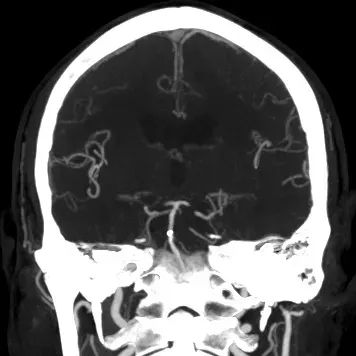

➢2024.07.09 入院急诊DSA:

造影见基底动脉中下段急性闭塞

造影见左侧优势椎动脉血流减慢

右侧椎动脉慢性闭塞

左侧颈内动脉无代偿

右侧后交通开放

术后4天,头颅CTA提示血管通畅。